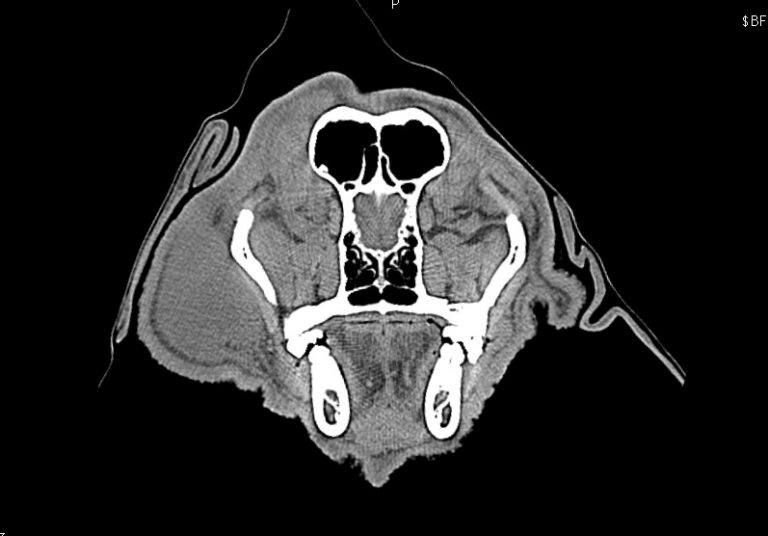

CT検査により外耳から中耳に至る腫瘤の存在が疑われ、耳道軟骨は骨化し、化膿巣は目の下から首にまで達していました。

耳道より前の腫れ、目の下にまで広がる